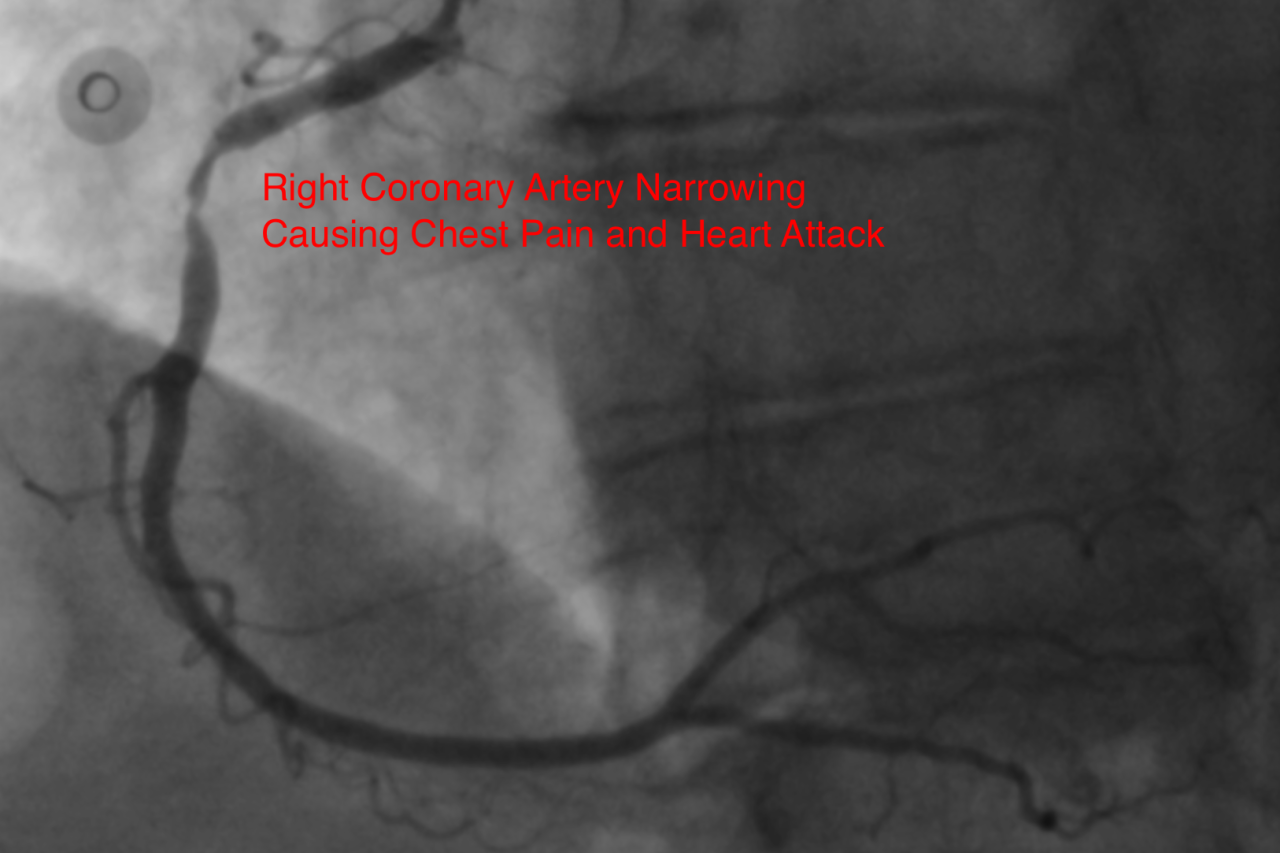

Right coronary artery narrowing causing chest pain and heart attack